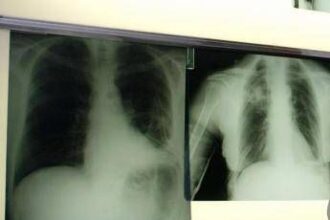

Giornata mondiale del tumore al polmone, PharmaMar: “Dal mare nuove armi per vincerlo”

Giornata mondiale del tumore al polmone, Novello (UniTo): “In Sclc la prima innovazione in 20 anni”

(Adnkronos) - “L’introduzione di un composto sintetico di origine marina nel trattamento…